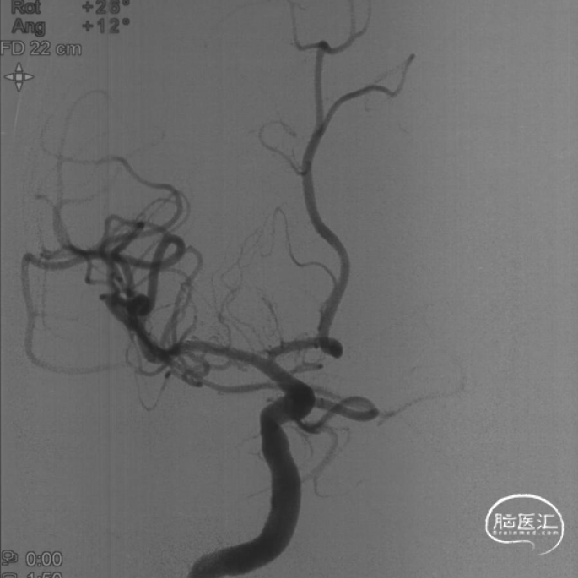

手术过程

6F Envoy DA导引导管到位,Synchro2微导丝通过病变。

选用1.5-9mm 颅内球囊扩张导管通过病变。

10atm扩张90s。

泄球囊后可见狭窄明显改善。

选用赛诺神畅 3.5-20mm COMETIU™自膨式颅内药物涂层支架系统通过病变并缓慢释放,释放后造影,支架定位准确,完全覆盖病变,成形效果好。

撤出导管导丝后造影,可见靶血管支架贴壁良好,前向血流通畅稳定。

2022-07-27 COMETIU™自膨式颅内药物涂层支架 3.5-20mm (正位)

2022-07-27 COMETIU™自膨式颅内药物涂层支架 3.5-20mm (侧位)